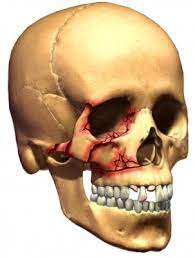

Maxillofacial Trauma

Maxillofacial injuries are frequent cause of presentations in an emergency department. Varying from simple, common nasal fractures to gross communition of the face, management of such injuries can be extremely challenging